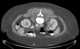

Benign symmetric lipomatosis is a skin condition characterized by extensive symmetric fat deposits in the head, neck, and shoulder girdle area. The German surgeon Otto Wilhelm Madelung was the first to give a detailed description of the disorder. [Source: Wikipedia ]

Diffuse lipomatosis of the neck

Lipomatosis